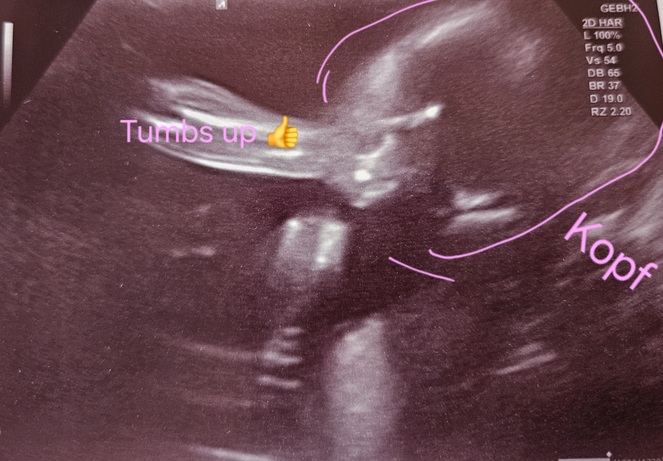

Der nächste Ultraschall steht an :) - Tagebücher aus der Schwangerschaft von Marie aus bei Heidelberg